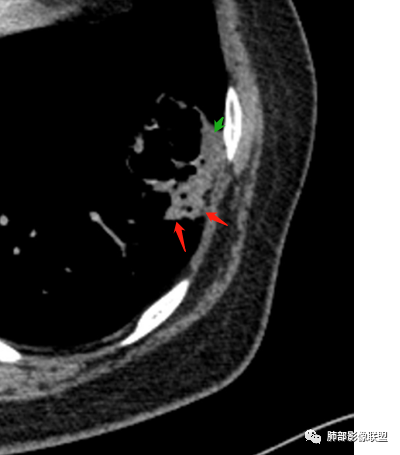

1、左肺下叶外基底段不规则囊腔样病灶,囊腔内有条形影及血管穿行。

2、囊壁薄厚不均匀,稍显僵硬,有壁结节(对应边缘分叶等)、结节强化明显。

以上两条几乎将肺囊肿彻底排除在外,且高度怀疑新生物!

3、灶周环以大范围磨玻璃影,非常均匀,没有重力分布趋势,分叶状,边界隐约可变。

4、冠状位部分层面可见支气管在囊腔边缘截断。

囊腔有张力,外形有分叶,壁厚薄不均,有间隔,有强化

胸CT:左肺下叶囊腔,壁厚薄不均,可见壁结节,囊腔内可见断裂小梁,部分融合,周围边界较清楚GGO,胸膜牵拉,可见血管集束、支气管充气征,冠状位部分层面可见支气管在囊腔边缘截断。考虑:囊腔型腺Ca。鉴别:肺大疱感染,CPAM等。